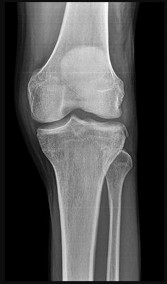

Question 9

A 72-year-old female on prolonged bisphosphonate therapy presents with thigh pain.

Radiographs show a fracture of the femoral shaft. Which of the following radiographic features is most characteristic of an atypical femur fracture associated with bisphosphonate use?

Explanation

Atypical femur fractures (AFFs) associated with prolonged bisphosphonate therapy have specific major criteria defined by the ASBMR. These include a location anywhere from just distal to the lesser trochanter to just proximal to the supracondylar flare, transverse or short oblique orientation, non-comminuted (or minimally comminuted), and originating at the lateral cortex with localized periosteal or endosteal thickening ('beaking').